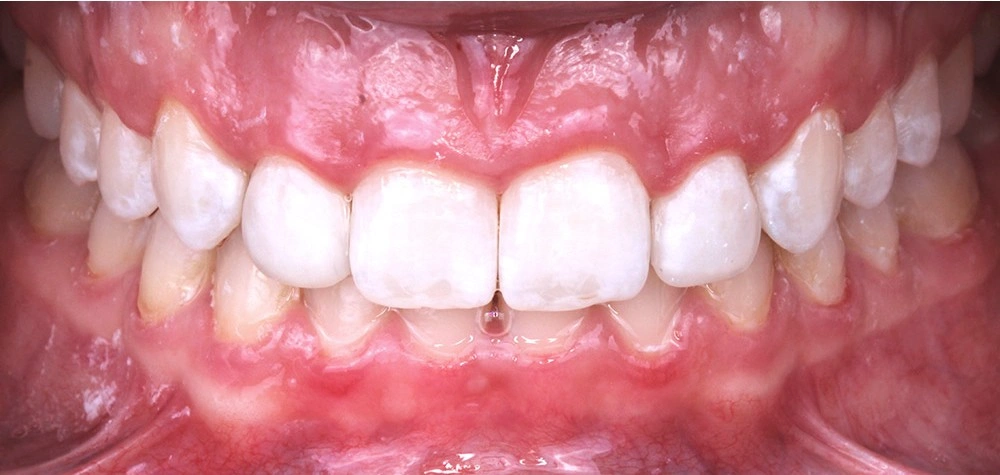

Глубокий прикус - Кейс 5

Эффективность устранения дефекта прикуса посредством элайнеров FlexiLigner.

Результаты лечения